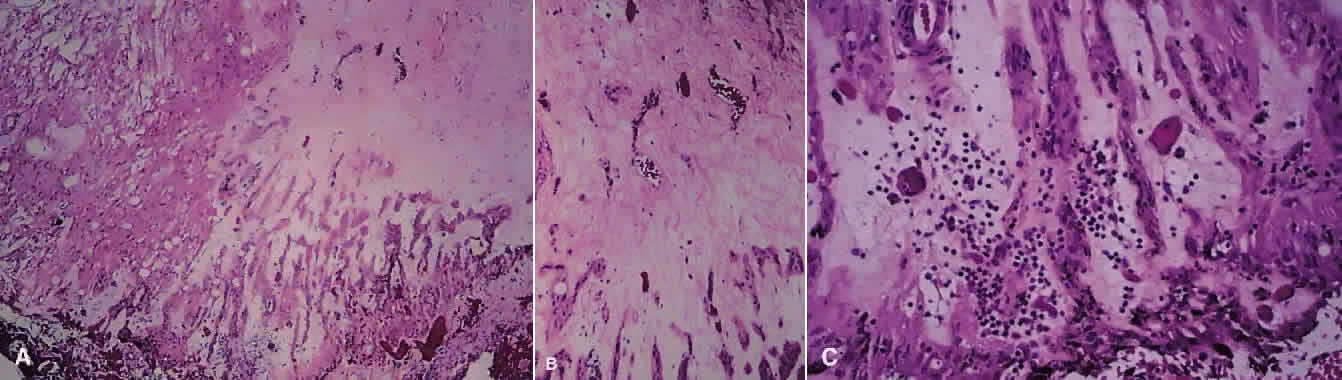

Histopathologic data about Behçet's uveitis come from a few pathologic reports on enucleated, blind, painful eyes with chronic disease.43 Light microscopy usually shows a panuveitis with infiltrating polymorphonuclear leukocytes, lymphocytes, plasma cells, and macrophages (Fig. 7). Immunohistochemical studies have shown a perivascular choroidal infiltration of activated CD4+ , but not CD-8+ , T cells,44,45 as well as focal aggregates of B cells and plasma cells, with increased expression of cell adhesion molecules on vascular endothelial cells.43 These findings imply a mixture of cellular and humoral components in the pathogenesis of Behçet's ocular vasculitis, in which CD4+ cells activate B cells, resulting in enhanced local production of antibodies and immune complex deposition.43 However, the nature of the antigen in the complex is not known.

Fig. 7. Photomicrograph from eye of patient with Behçet's disease showing infiltration of retina with acute and chronic inflammatory cells, especially in the perivascular region (hematoxylin and eosin; × 400). (Photomicrograph courtesy of Professor Hajime Inomata, Kyushu University, Fukuoka, Japan.)

Much attention has been given to the histopathologic nature of the “snowbanks,” which has been studied by both light and electron microscopy.52,54,56–58 These fibrovascular-glial proliferations are found over the inferior pars plana and peripheral retina. They are composed of dense connective tissue derived from condensed, collapsed vitreous and often are vascularized. These vessels may reveal features of high endothelial venules (Fig. 8). Such endothelia are known to play a role in the homing of activated lymphocytes.54 The cellular elements of these membranes include fibroglial cells that are believed, based on their electron microscopic characteristics, to represent fibrous astrocytes, as well as nonpigmented ciliary epithelial cells, fibroblasts, and lymphocytes (Fig. 9).52–55,59,60 The vitreous is infiltrated by chronic inflammatory cells, and despite the nongranulomatous nature of the inflammatory component in the snowbanks, vitreous snowballs have been reported to consist of epithelioid cell granulomas.52

Fig. 9. A. Photomicrograph of “snowbank” in patient with pars planitis showing a fibroglial mass with proliferated epithelial elements (hematoxylin and eosin; × 31). B. Higher magnification showing epithelial elements and glial proliferation (hematoxylin and eosin; × 80). C. Chronic inflammatory cell infiltrate in pars planitis (hematoxylin and eosin; × 200).